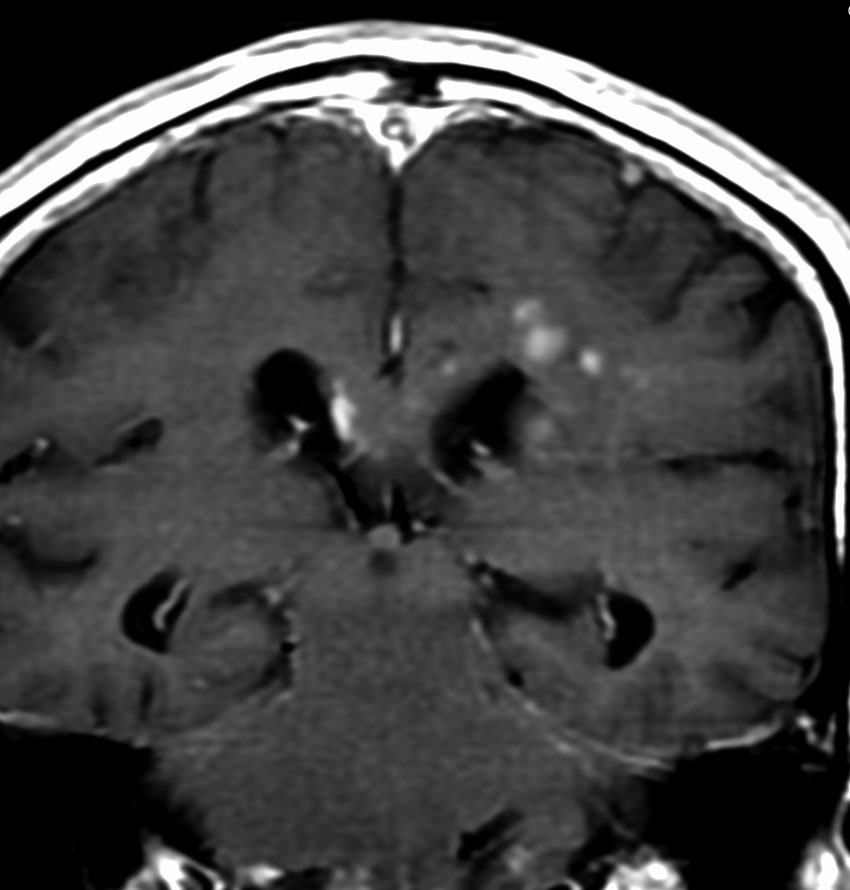

MRI画像所見 60代で嚥下障害と構音障害で発症した例

延髄から中脳まで腫瘍があって脳幹部が腫れています。この画像ですと,小児のびまん性橋膠腫(DIPG,びまん性正中グリオーマ)のように見えます

両側視床から大脳基底核,両側大脳半球深部白質,脳梁まで広範囲に腫瘍が存在します。退形成性星細胞腫のようにまだらにガドリニウム増強されます。